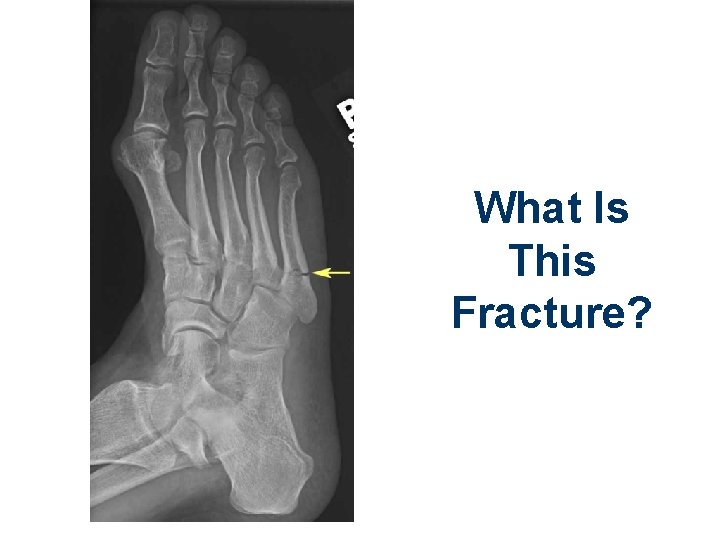

What Is This Fracture?

Metatarsal Fracture. How Should It Be Immobilized?